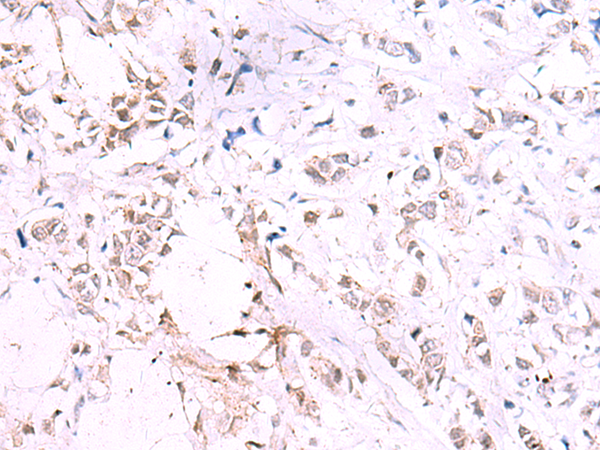

分类: 科研抗体货号: P13586别名: ABBP1; HNRPAB应用: WB,IHC反应种属: Human, Mouse